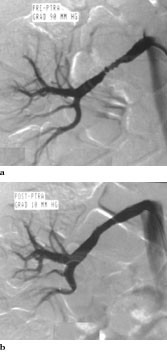

Figur 1 viser et eksempel på renal angioplastikk ved typisk fibromuskulær dysplasi. Figur 2 viser en bilateral subtotal arteriosklerotisk nyrearteriestenose før og etter angioplastikk. Vellykket initial revaskularisering og godt akutt resultat av alle stenosene hos pasienten ble oppnådd hos 92 %, mens det hos ytterligere 4 % ble oppnådd bedring. Det var 14 (5 %) mislykkede forsøk hos pasienter med arteriosklerotisk sykdom. En pasient med fibromuskulær dysplasi måtte opereres neste dag pga. mislykket prosedyre. Det var fem mislykkede forsøk hos de transplanterte (7 %). Før bruk av stent forelå det en høy restenoserate, særlig for ostiale stenoser (39 % restenose), men sluttresultatet kunne bedres betydelig ved å gjenta utblokkingen (tab 1). Segmentalgrener og små arterier med diameter< 5 mm kom dårligst ut. Pasienter med fibromuskulær dysplasi kom bedre ut enn de øvrige pasientene.